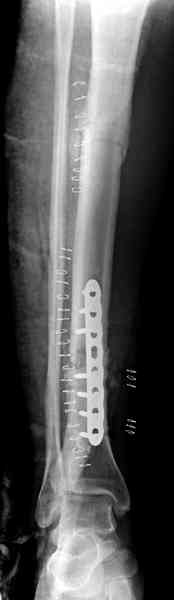

Недавно на нашей ежемесячной Morbidity&Mortality

conference мы разбирали похожий случай, ложный сустав большеберцовой кости после резекции опухоли.

К нашему онкологу-ортопеду обратился больной с жалобами на боли в голени, из рассказа - год назад была сделана биопсия большеберцовой кости, но название заболевания "не запомнил”.

Оперирован в военном госпитале с заменой сегмента

аллокостью большеберцовой кости и после демобилизации явился для постоянного наблюдения по месту жительства.

Наши имели проблему со сращением, пришлось им сделать динамизацию, дополнительную аутопластику.

Снимки представлены.